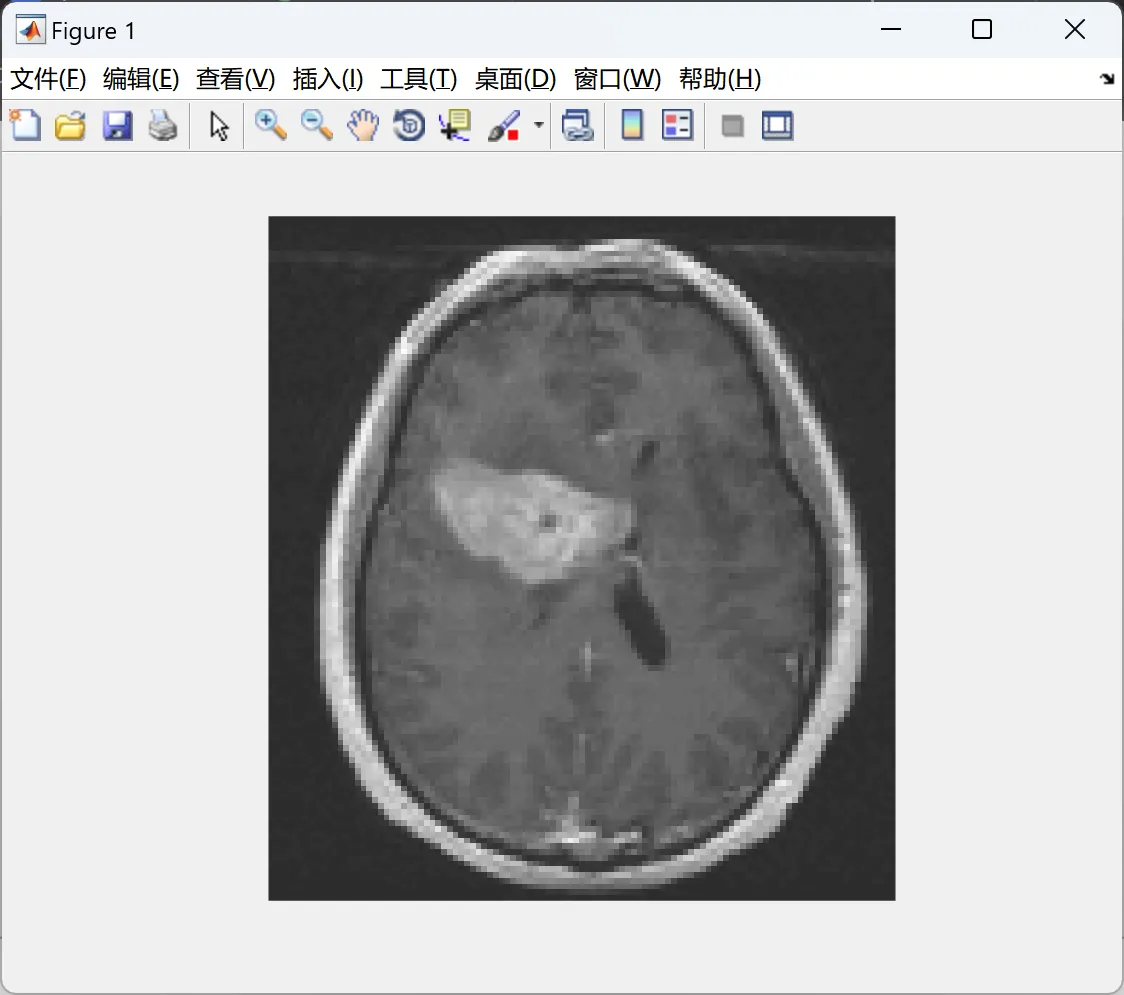

• 抗灰度不均匀性:成功分割脑MR图像中强度渐变的灰质/白质。

• 医学影像

• 肝脏CT肿瘤分割:通过局部方差差异定位病灶。

• 脑MR多组织分割:扩展多相LGDF模型划分灰质、白质、脑脊液。

📚2 运行结果

2.2 测试2

image.gif 编辑